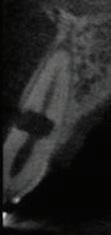

This element was not stimulated with the cold test and the radiographic image revealed an incomplete endodontic treatment (Figs. 1-2). The element seemed to present a suitable root length for a conservative restoration, but the apical position of the carious lesion and the proximity of the interdental bone ridge didn’t allow a correct rehabilitation with prosthetic crown, respecting the biological width.2

Figure 2: Initial radiograph showing endodontic dressing that had been present for some months, but the treatment was never completed. Note the depth of the caries lesion and the proximity of the interdental bone ridge, which may represent an obstacle for prosthetic rehabilitation.

The canal was sealed with a Thermafil™ cone (Dentsply Sirona) with an apical diameter of 0.30 mm (Figs. 3-4).